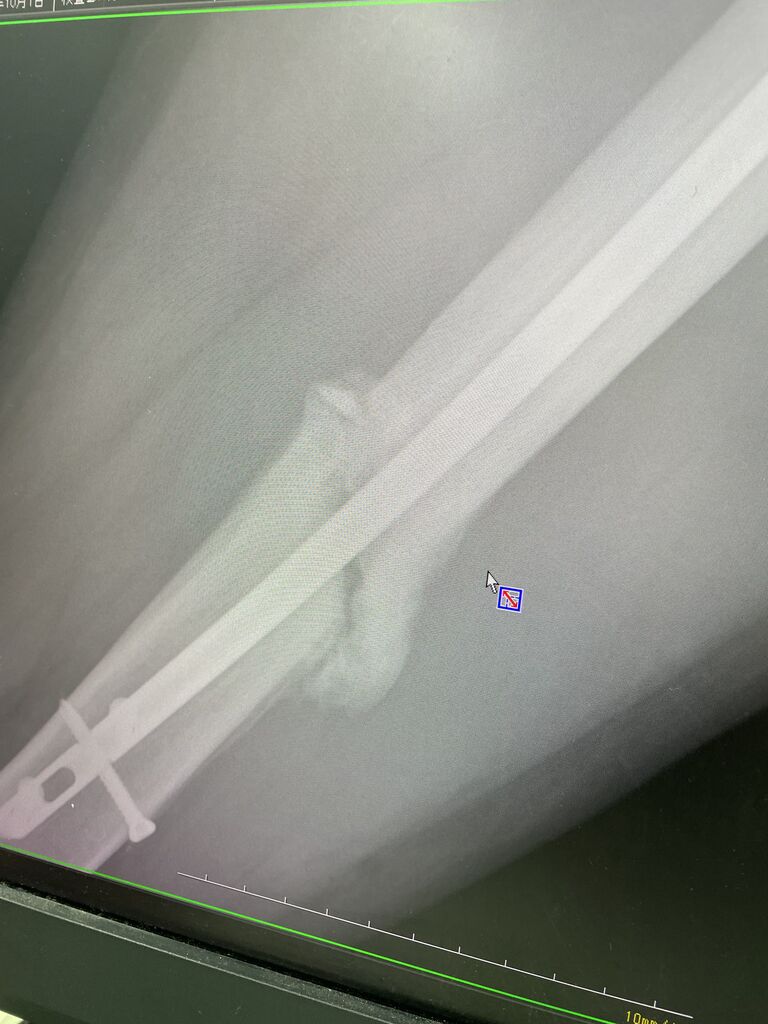

モトクロスプロライダー

大腿骨骨折をして4ヶ月が経ちます

ぼちぼち、ライディングのリハビリ開始です

強いい気持ちを持って、夏を開けてからレースに参戦す

るかもしれません

だんだんメニューを組んで復帰させたいと思います